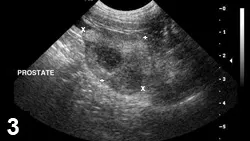

Featured Image

FIGURE 3

Prostatitis with abscess. Sagittal view of an intact canine prostate (cursors); a hypoechoic nodule is visible within the parenchyma. The parenchymal echo texture is mixed.

• Septic prostatitis is best diagnosed by abdominal ultrasonography with guided fine-needle aspirates for cytologic examination and culture, giving specific attention to cystic structures within the parenchyma.

• Ultrasonographic findings are nonspecific but typically will be of mixed echotexture with hyperechoic areas reflecting fibrosis (Figure 3).